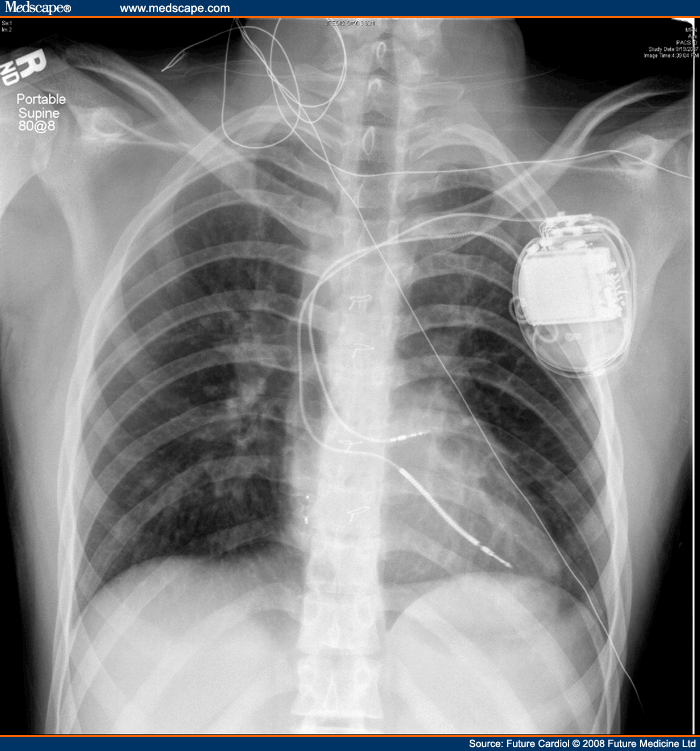

From www.medscape.com

Pacemaker and Defibrillator Therapy in Peds and Congenital Heart Disease Defibrillator Therapy Complications     — the most common major complications were lead dislodgement (10 events; Hypertrophic cardiomyopathy (hcm) has different complications such as cardiac arrhythmia.    — no major intraprocedural complications were reported. The food and drug administration (fda) has recently accepted a widely proven and patient. At 6 months, 25 major complications were observed, in 23 of 316. 1 currently, crt alone. Defibrillator Therapy Complications.